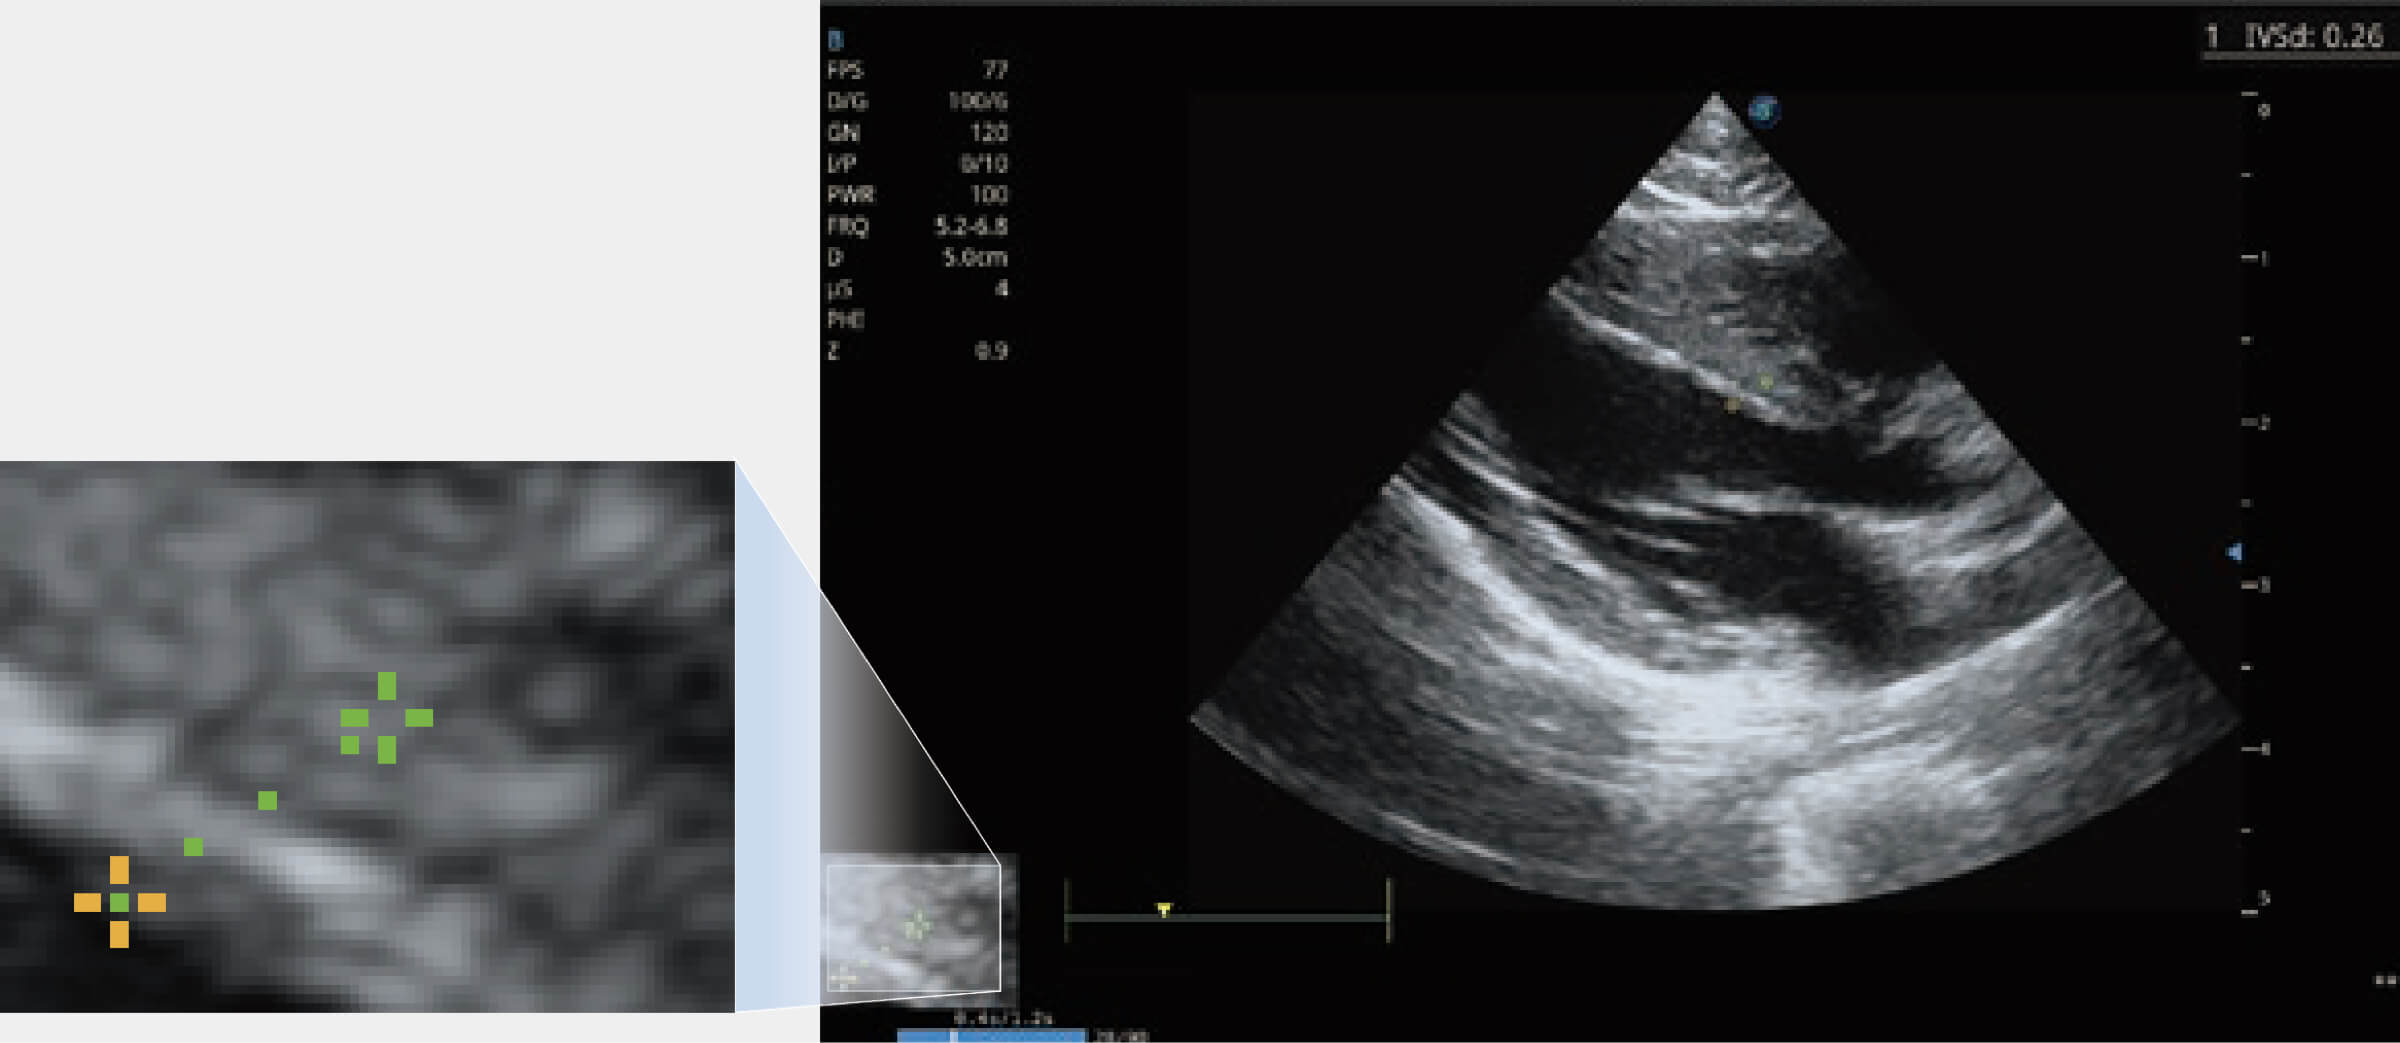

ProPet 70 進(jìn)一步提升了微米成像算法,更加注重對(duì)基礎(chǔ)原始圖像的還原和保留,在有效減少斑點(diǎn)噪聲、增強(qiáng)組織邊界顯示的同時(shí),避免過(guò)度優(yōu)化丟失真實(shí)的解剖信息。

增強(qiáng)穿刺針在動(dòng)物解剖結(jié)構(gòu)中的位置,提高穿刺介入的安全性和準(zhǔn)確性。

通過(guò)360度任意調(diào)節(jié)3條M型取樣線,在同一心動(dòng)周期上觀察心臟不同位置的運(yùn)動(dòng)曲線,得到準(zhǔn)確的心功能測(cè)量數(shù)據(jù),有效評(píng)估心肌運(yùn)動(dòng)及左心室功能。

當(dāng)心臟測(cè)量結(jié)果超出正常范圍時(shí),可實(shí)時(shí)預(yù)警提示動(dòng)物醫(yī)生,減少疾病漏診概率。